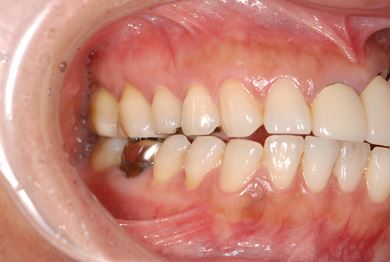

| 性別/年齢 | 女性 / 45歳 | ||||||||||||||||||||||||||||||||

| 主訴 | 以前治療した歯の歯ぐきから出膿。他の歯科でインプラントかブリッジしか方法がないが、骨の状態からインプラント治療は無理かもしれないと言われたことに不安を感じ、セカンドオピニオンを求めて来院。 | ||||||||||||||||||||||||||||||||

| 治療方針 | 保存不能の歯を抜歯し、インプラント治療にて機能的・審美的回復を行う。 | ||||||||||||||||||||||||||||||||

| 治療内容 | インプラント1本、ハイブリッドセラミッククラウン1本 | ||||||||||||||||||||||||||||||||

| 総治療費 | 310,905円 | ||||||||||||||||||||||||||||||||

| 治療期間 | 5ヶ月 |